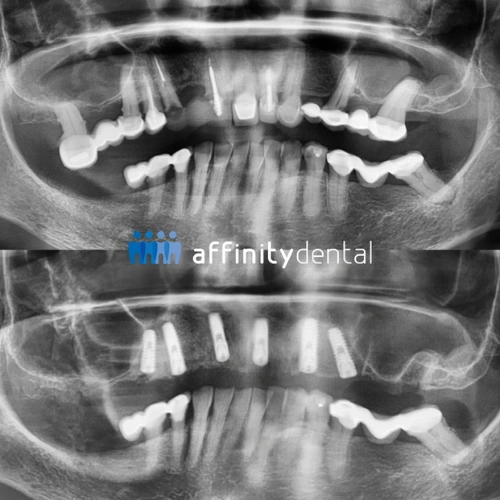

We begin with a comprehensive clinical evaluation and 3D imaging using Cone Beam CT and intraoral scanners. This helps us assess bone quality, design your custom surgical guide, and simulate the entire procedure in advance.

Implants are precisely placed based on the digital treatment plan. If the bone is sufficient and implant stability is achieved, we proceed with immediate restoration.

While you wear your temporary teeth, your implants will osseointegrate over 3 to 6 months. During this period, we monitor progress and ensure everything remains stable.

Once healing is complete, your permanent zirconia crowns or bridges are placed—offering exceptional durability, comfort, and beauty for many years to come.